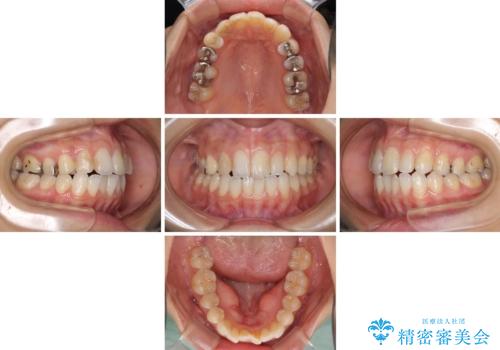

- 中学生の時に矯正治療をしたものの、後戻りを気にして来院された患者様です。

骨格的に下顎が右側に変位しているため、左右の咬み合わせを理想的なものに改善することはできませんが、インビザラインにて歯列を整えることとしました。

骨格的なズレによる左右差は改善できませんでしたが、上下の正中を極力合わせるようにすることができました。